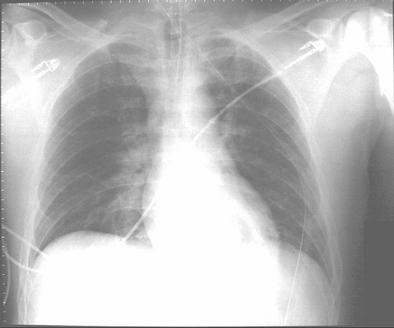

Before transfer to the Burn Unit, the paramedics intubated the patient in the field and irrigated his eyes with water. A nasogastric tube and an indwelling urinary catheter were also placed. His examination at the Burn Unit showed conjunctival erythema, lacrimation, thick nasal discharge, wheezing, pharyngeal erythema and second-degree skin burns (see Figure 1). His initial laboratory reports were within normal limits. His arterial blood gas drawn on Assist Control mode of ventilation with a tidal volume of 8 cc/kg body weight, set respiratory rate of 12/min with patient rate at 14/min, PEEP of 5 and FiO2 of 40% showed a pH of 7.48, a PaCO2 of 32 mmHg and a PaO2 of 70 mmHg. His chest X-ray portable anteroposterior view is shown in Figure 2.

Figure 2. Chest X-ray portable anteroposterior view.